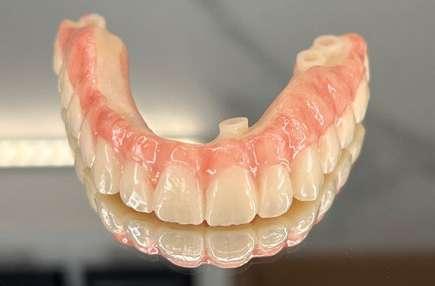

Fase 2: corrección con alineadores Una vez corregida la discrepancia transversal y finalizado el periodo de control, el tratamiento continuó con alineadores Spark™, con un protocolo de uso de 22 horas diarias y cambios de alineadores cada 10 días. El tratamiento con alineadores se planificó en 2 etapas. Una primera etapa para abordar el plano vertical y una etapa final para abordar el plano sagital.

Corrección vertical (Ilustración 7):

 Extrusión de incisivos superiores (1,7 mm) e inferiores (1,5 mm) con attachments de control radicular.

 Intrusión de molares mandibulares mediante turbo bites para facilitar el cierre de la mordida.

Como se puede apreciar en las imágenes adjuntas, la corrección vertical planificada se logró en su totalidad. En esta etapa, se colocaron carillas provisionales de composite de canino a canino en la arcada superior para mejorar la estética del paciente y compensar la discrepancia de Bolton (Ilustración 8). Para la corrección sagital se fabricó un nuevo juego de alineadores transparentes.